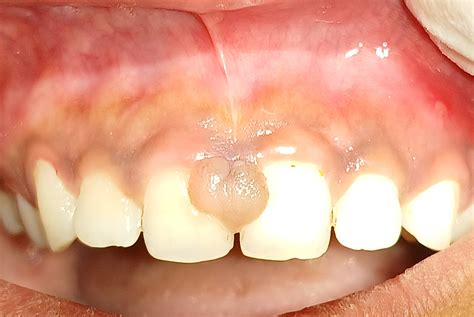

¿Cómo es un Fibroma?

Las características de la hiperplasia fibrosa focal son las siguientes:

- Aparece una masa o tumor con base sésil, es decir, que no tiene tallo y está unido a la superficie. También puede ser pediculada, con tallo.

- Tiene un aspecto carnoso, con forma redonda u ovalada. Si crece debajo de una prótesis, la superficie será plana.

- La masa suele ser blanda o dura y estar cubierta de un epitelio escamoso estratificado.

- Tiene un color rosa, similar al del resto del tejido oral, aunque debido a la falta de vasos sanguíneos puede ser más claro.

- Su crecimiento es lento y el tamaño suele ser entre 1 y 1,5 centímetros; sin embargo, puede crecer más de eso y en este caso hablamos de fibromas gigantes.

- Los tumores son asintomáticos, aunque pueden generar molestias por su ubicación y tamaño. Además, debido al roce constante pueden ulcerarse.

- Por otra parte, son benignos y no evolucionan a un fibroma bucal maligno.